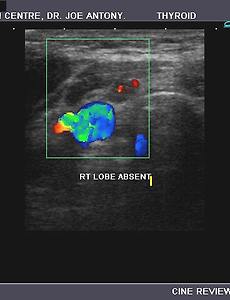

Hemiagenesis of the thyroid 1) absence of the right lobe of thyroid 2) normal or slightly enlarged left lobe and isthmus of thyroid This 18 yr. old female patient presented with symptoms of hypothyroidism. On sonography of the thyroid, we observed: 2) normal or slightly enlarged left lobe and isthmus of thyroid c) mild to moderate augmentation of vascularity of the left lobe on color doppler imaging. These ultrasound image.. 2009. 9. 14. 이전 1 다음